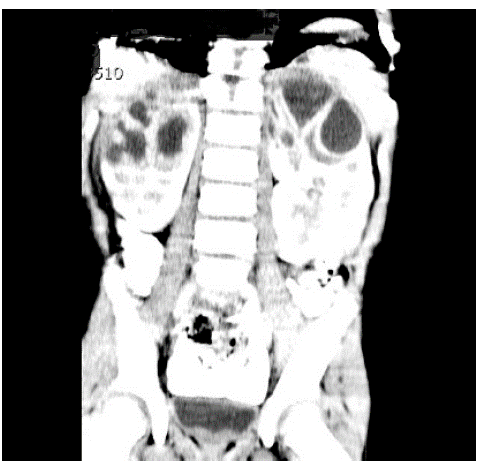

Al inicio, no se solicitaron estudios de imágenes renales mientras se analizaban los tomados en las ITU previas. A las 48 horas de manejo, el paciente persistía con picos febriles, por lo que se decidió llevar a cabo otros estudios complementarios como función renal, cuyo resultado estuvo dentro de límites normales, y una ecografía renal y de vías urinarias que reportó una imagen sugestiva de pielonefritis bilateral de los polos superiores sin poder descartar presencia de abscesos incipientes. Se dispuso continuar con la administración del mismo antibiótico hasta tener el reporte de urocultivo y solicitar una escanografía de abdomen (Figura 1), que reveló lesiones focales hipodensas que comprometen las pirámides de ambos lóbulos superiores de los riñones, las cuales podían relacionarse con proceso infeccioso.

Respecto a los estudios por imágenes, la realización de una ultrasonografía renal es una buena decisión en el estudio inicial de los abscesos renales. Sin embargo, este no puede diferenciar un absceso de una pielonefritis no complicada 10. Frente a la ecografía, la tomografía tiene un rendimiento superior para el diagnóstico de absceso renal o perirrenal con una precisión del 90% al 100%. Esta investigación contribuye a aclarar los casos clínicos dudosos y a la evaluación del tamaño de los abscesos renales. En muchas ocasiones, la TAC es necesaria para caracterizar las lesiones 10; este fue el caso de la presente investigación.